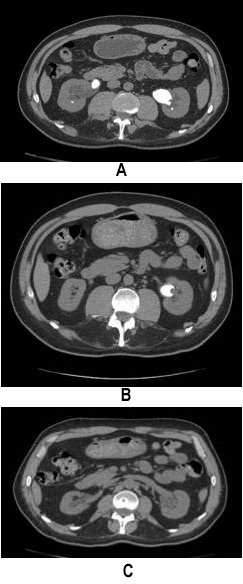

Эффективность цитратной терапии в лечении МКБ подтверждают результаты различных исследований, однако наиболее яркое подтверждение целесообразности ее назначения можно найти в сообщении М. Barbera и соавт. (2016), представленном на 20-м Национальном конгрессе SIEUN. Итальянские врачи рекомендовали 59-летнему мужчине, у которого при проведении компьютерной томографии (КТ) без контрастирования обнаружены конкременты в правой (размером 30×20 мм, плотностью 400 HU) и левой (40×30 мм, 500 HU) почке (рис. 1А), длительный прием цитрата для ощелачивания мочи.

Спустя 4 месяца лечения медики не только констатировали изменение рН мочи, но и отметили исчезновение конкремента в правой почке и значительное уменьшение в размерах литолита в левой почке (рис. 1В). Через 7 мес. на контрольных КТ-сканах ни в одной почке не выявлено ни одного конкремента (рис. 1С). Итальянские специалисты отметили хорошую переносимость цитратной терапии: несмотря на наличие значимой сопутствующей патологии (сахарного диабета, ишемической болезни сердца), прием цитрата не сопровождался появлением нежелательных явлений.

Рис. Эффективность 7-месячной цитратной терапии в лечении уролитиаза (Barbera M. et al., 2016)